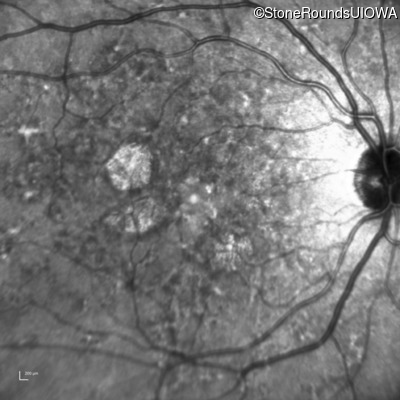

Infrared Fundus Photograph - Right - 20/20

Exemplar

Infrared Fundus Photograph - Left - 20/20 -1